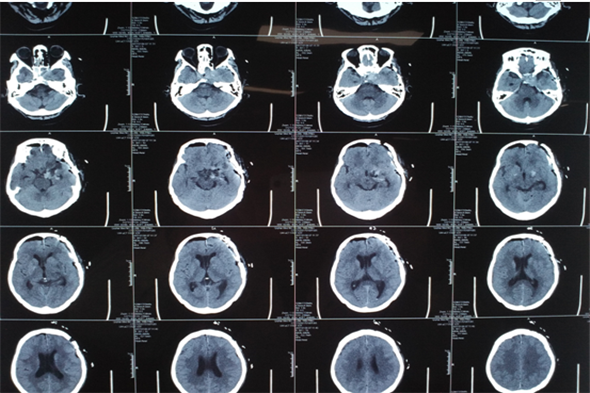

当日,先由麻醉医生为患者麻醉,在手术室护士的密切配合下,由吴卫东主任为患者施行手术,术中吴卫东主任凭借精湛的手术技能,在开颅切除蝶骨脊旁5.0cm肿瘤后,在狭小的动脉与各个神经缝隙间精细操作,以刮匙完全刮除鞍内肿瘤,保留周边血管及神经,手术进行的十分成功,在术后的第一天患者就意识清醒,无功能缺失。

垂体瘤在临床出现症状较多,主要是肢端肥大,巨人症及库欣氏综合征,亦可出现泌乳或性功能低下等症状,垂体瘤从形态上可分为:微腺瘤、大腺瘤、巨大腺瘤。超过3cm即为巨大腺瘤,该患者肿瘤直径为5cm,为巨大腺瘤。其周围为颈内动脉,视神经及动眼神经等重要组织结构,手术风险较大,神经外二科成立以来垂体瘤切除术已是常规手术,但此巨大垂体瘤实属罕见。吴卫东主任精准的判断及娴熟的手术技巧,神经外二科团队及麻醉科快速、高效的配合再一次创造了奇迹。

术后CT